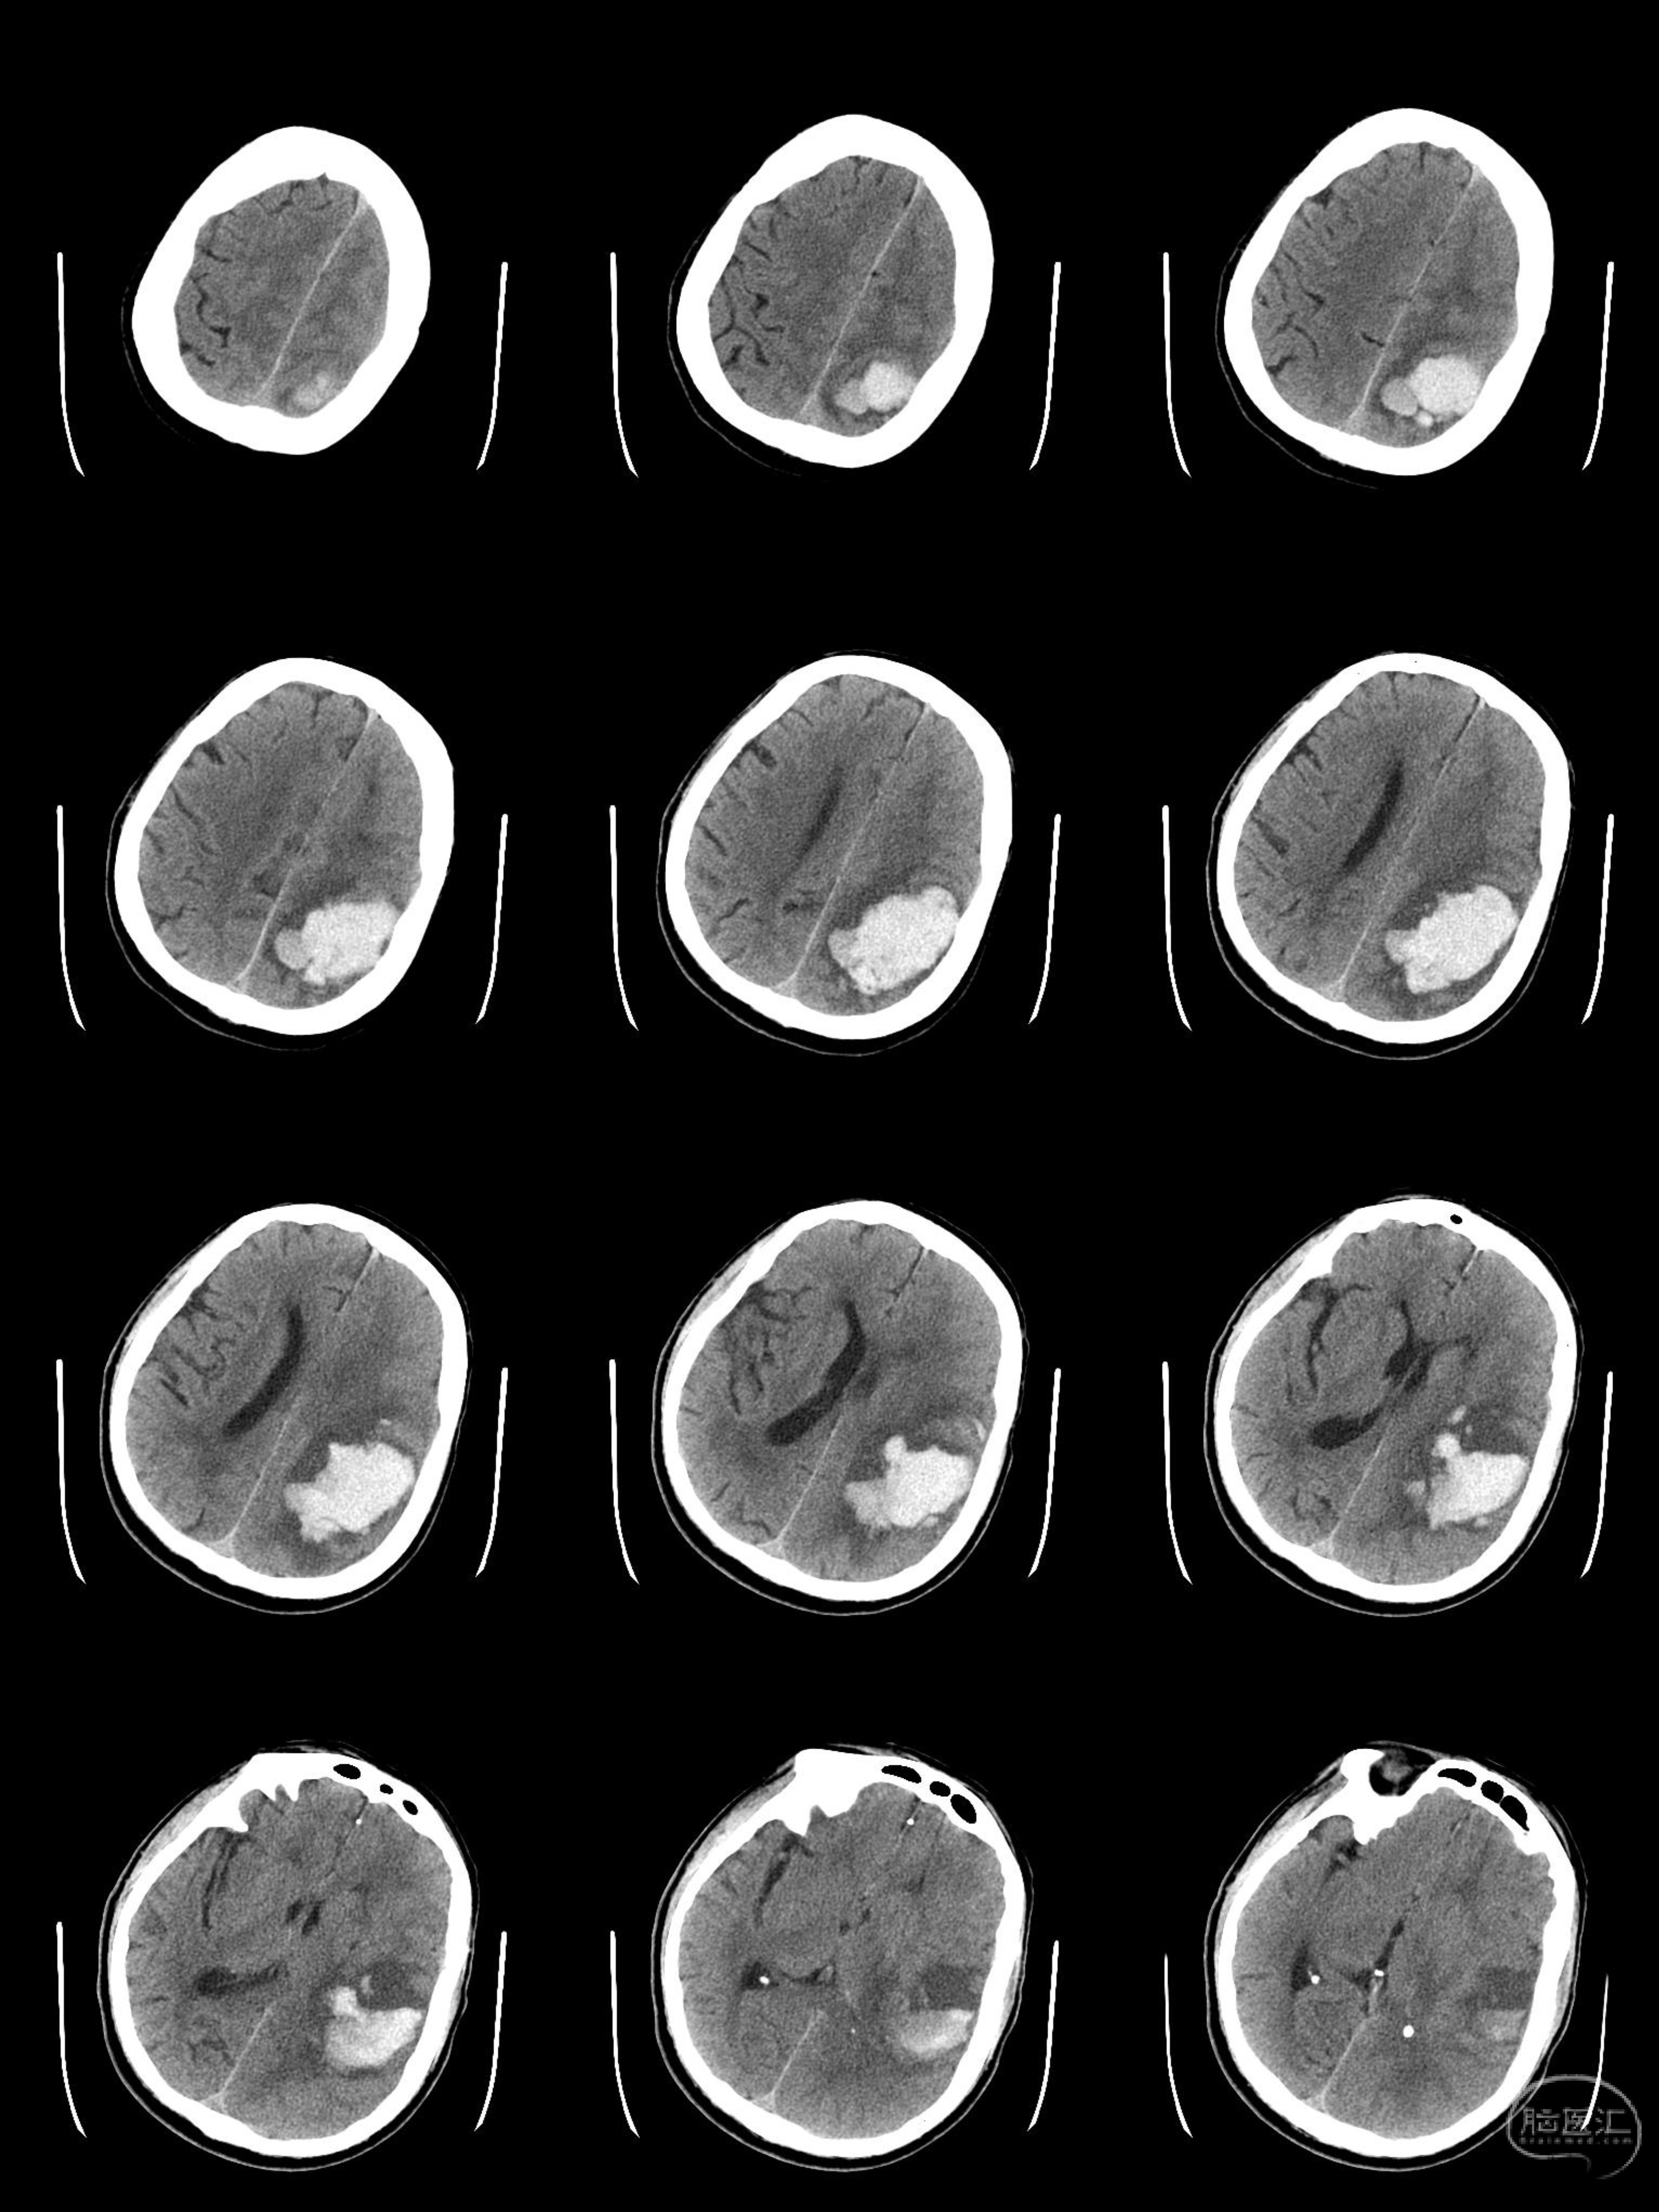

术前CT提示左侧顶叶出血,血肿主体主要位于中央沟以后,量约60ml,手术指征明确